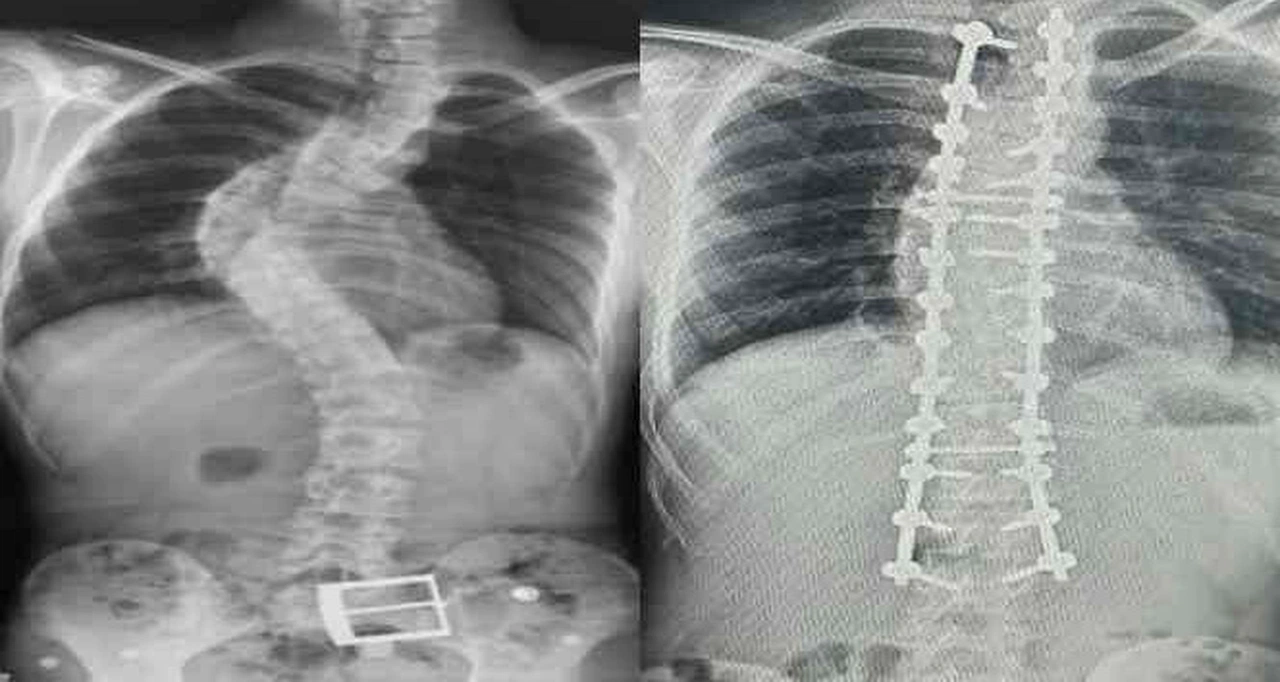

Dr. Yüksel, erken teşhis sonrası tedavi sürecinin korkulacak bir süreç olmadığını belirtti. "10-20 derece arası eğriliklerde özel egzersizler ve takip yeterli oluyor. 20-40 derece arasında ise egzersize ek olarak korse tedavisi uyguluyoruz. 40 derecenin üzerindeki ileri vakalarda ise cerrahi yöntemler gündeme geliyor," diyerek tedavi yol haritasını özetledi.